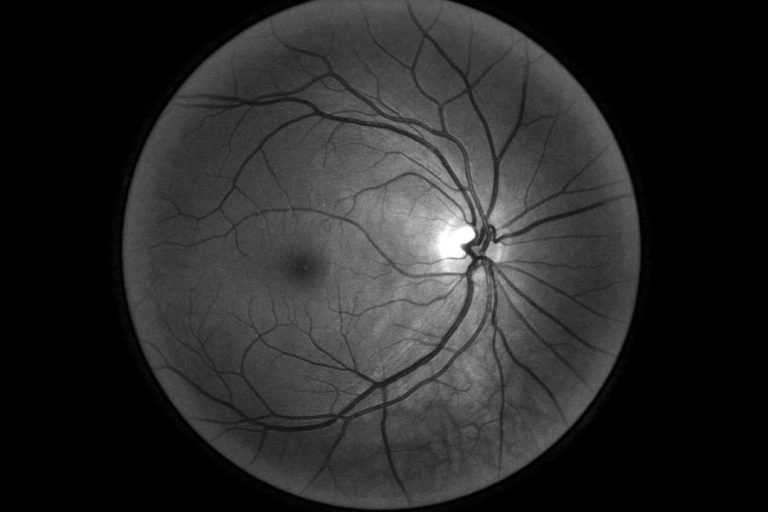

في النظام الذي كانت تستخدمه تايلاند، تلتقط الممرضات صوراً لأعين المرضى أثناء إجرائهم الفحوصات، ويُرسلنها ليتم فحصها من قِبل أخصائي موجود في مكان آخر، وهي عملية قد تستغرق ما يصل إلى 10 أسابيع. ولكن يمكن للذكاء الاصطناعي الذي طوّرته جوجل هيلث تحديدُ علامات اعتلال الشبكية السكري من خلال فحص العين، بدقة تزيد عن 90%، وهي الدقة التي يطلق عليها الفريق "مستوى الأخصائي البشري". ومن حيث المبدأ، تظهر نتيجة هذا الفحص في أقل من 10 دقائق. ويحلل النظام الصور بحثاً عن مؤشرات تدل على الحالة، مثل انسداد الأوعية الدموية أو تسرب الدم منها.

مصدر الصورة: جوجل